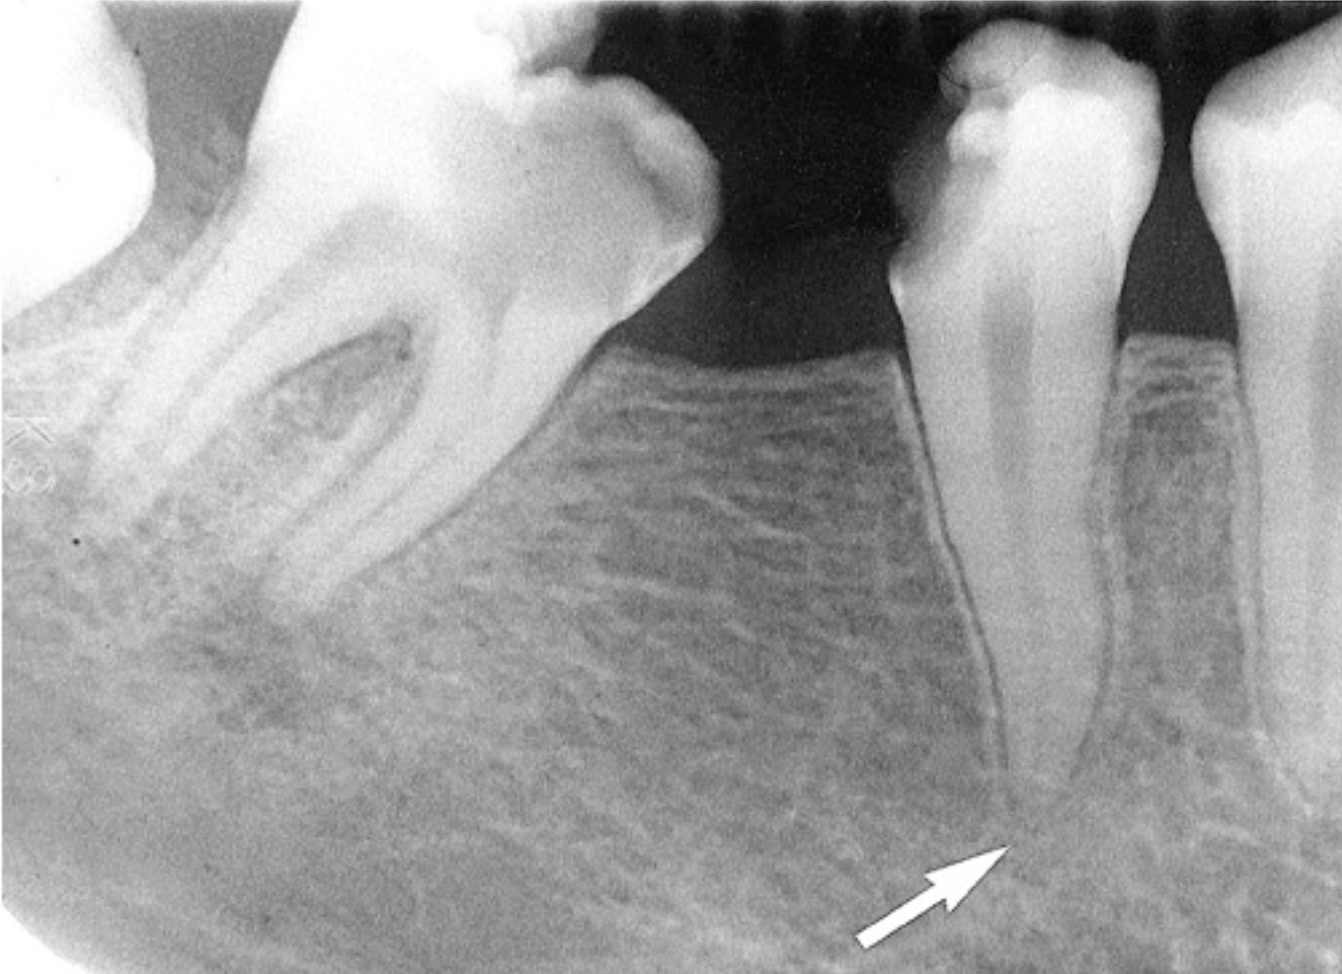

widening of PDL space

loss of lamina dura definition

different radiographic presentations of apical periodontitis

early lesions → subtle changes in periapical tissues

long-standing lesions → radiolucency at root apex with surrounding radiopacity

imaging appearance varies on disease stage and bone response